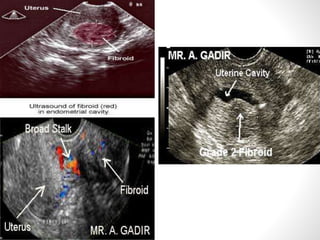

Fibroids (leiomyomas) are benign smooth muscle cell tumors of the uterus that are commonly found in women. They vary in location within the uterus and can cause symptoms like bleeding, infertility, pain, and abdominal enlargement. Fibroids are typically diagnosed through ultrasound, hysteroscopy, or other imaging tests. Treatment options depend on a woman's age, parity, number of fibroids, and symptoms, and may include medication, myomectomy, hysterectomy, or uterine artery embolization. Fibroids can complicate pregnancy by increasing risks of abortion, preterm labor, pain, and cesarean section.